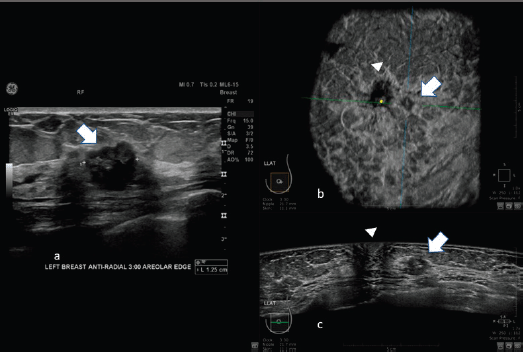

Images of comparison between ABUS, HHUS and mammography are shown in Figures 2 and 3.

Figure 2. 62-year-old patient with biopsy proven left breast carcinoma. a: Hand-held ultrasound showing the lesion (arrow). b: 3D ultrasound (ABUS) image at the dedicated workstation. Reconstructed coronal plane: the lesion is marked with the arrow; the nipple is marked with the arrowhead. c: reconstructed axial plane of Automatic Breast Ultrasound (ABUS): the lesion is marked with with the arrow; the nipple is marked with arrowhead.